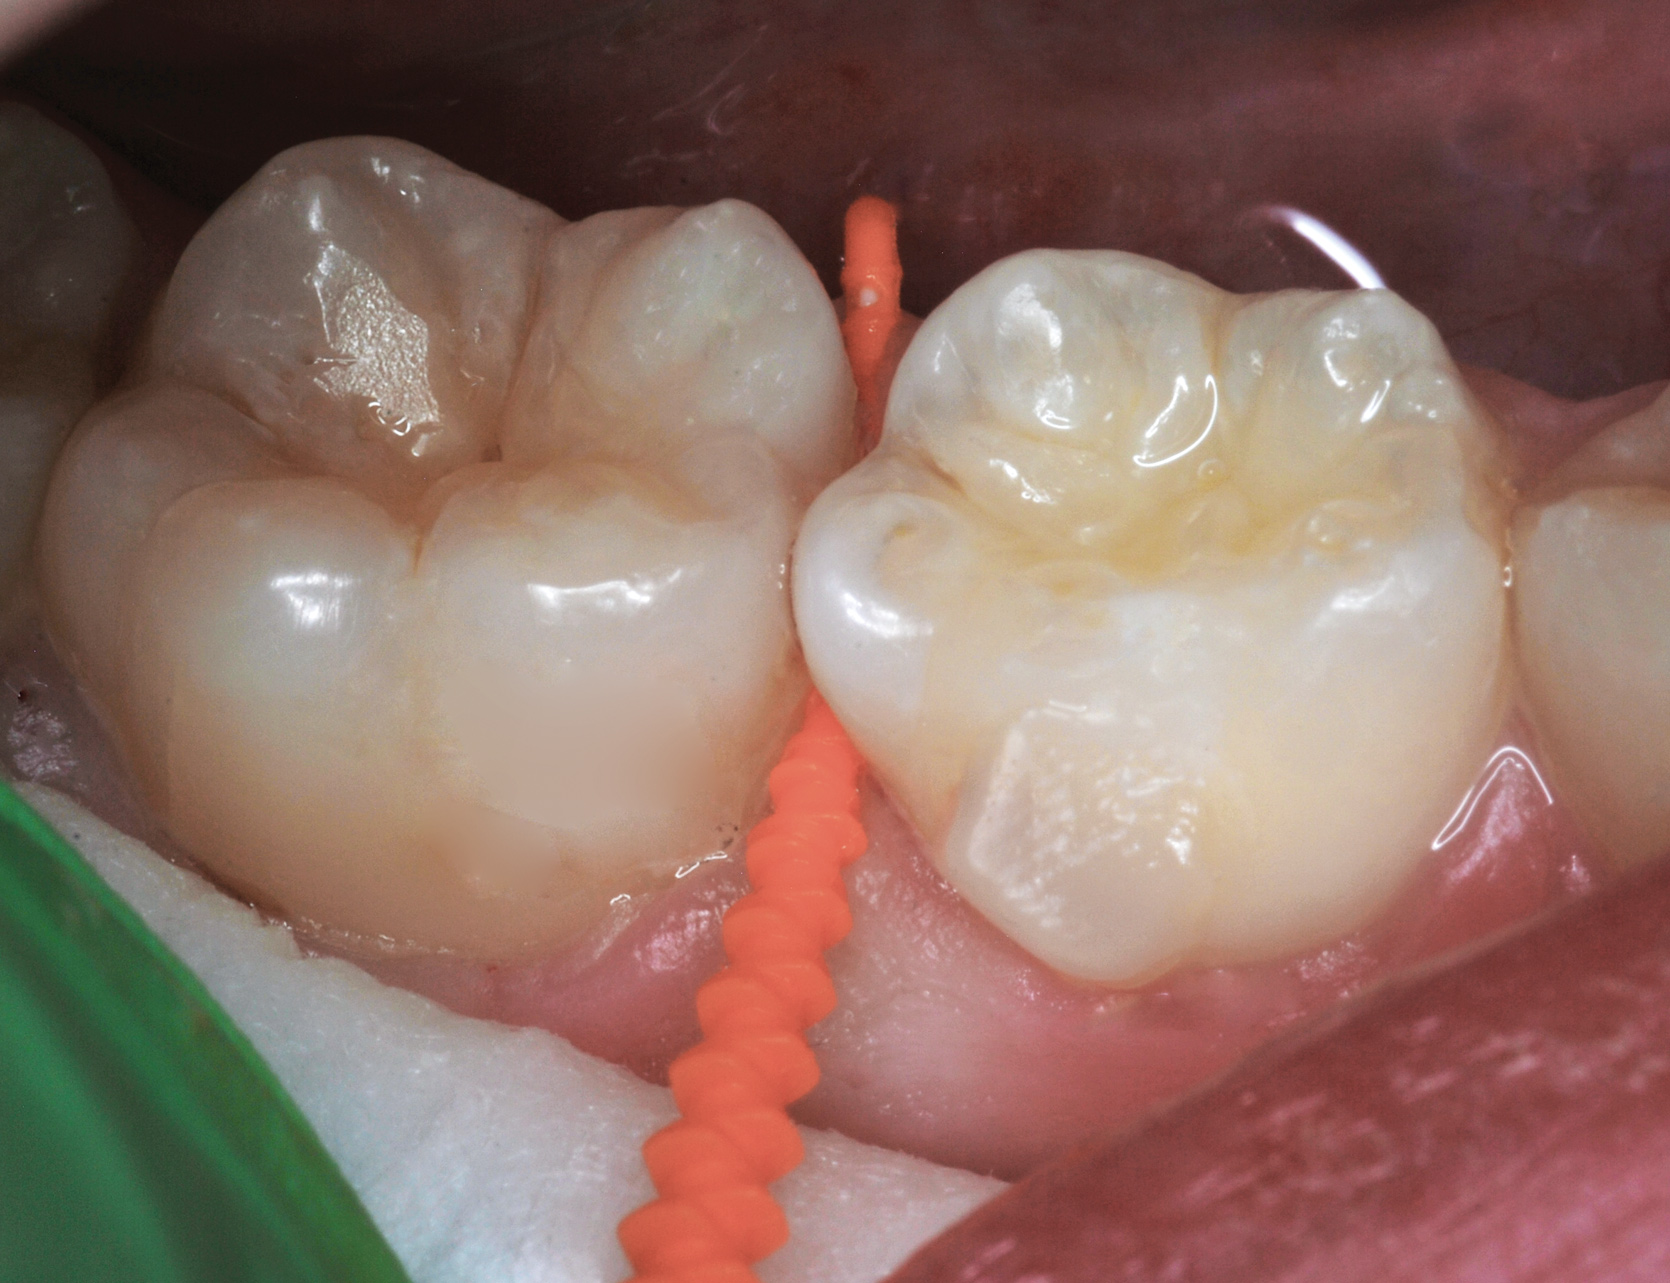

Fig 3. Three thin soft dental picks were used simultaneously for SDF proximal surface saturations in a teenaged patient (Fig 3). After 60 seconds, the treated regions were covered with 5% fluoride varnish (Fig 4). A comparison can be seen of pre-SDF-treatment bitewing films (Fig 5) and 8-month post-SDF bitewing films (Fig 6) for the patient shown in Fig 3 and Fig 4. Radiolucencies were similar or improved, except for contact of maxillary first and second molars.

Fig 4. Three thin soft dental picks were used simultaneously for SDF proximal surface saturations in a teenaged patient (Fig 3). After 60 seconds, the treated regions were covered with 5% fluoride varnish (Fig 4). A comparison can be seen of pre-SDF-treatment bitewing films (Fig 5) and 8-month post-SDF bitewing films (Fig 6) for the patient shown in Fig 3 and Fig 4. Radiolucencies were similar or improved, except for contact of maxillary first and second molars.

Figure 4